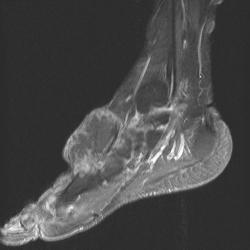

сагиттальная Т2

На серии МР-томограмм получены изображения правого голеностопного сустава.

На тыльной поверхности правой стопы, непосредственно под кожей в области таранной, ладьевидной, клиновидных и оснований от первой до третьей плюсневых костей определяется патологическое образование (тофусы), с распространением на медиальную поверхность стопы, образование неоднородной структуры и МР-сигнала, умеренно гиперинтенсивное на Т1 ВИ, гипоинтенсивное на Т2 ВИ и неоднородного на FAT SAT ИП. Размеры образования 35 х 65 х 40 мм. На постконтрастных изображениях отмечается значительное диффузное усилением интенсивности МР-сигнала от образования. Аналогичные по МР-характеристикам образования, меньших размеров выявляются в левой стопе.

Со стороны костной системы определяются: единичные костно-хрящевые дефекты со склерозом по периферии, диаметром до 3 мм, располагающиеся в субхондральных отделах в области суставных концов большеберцовой и малоберцовой костей, в области прикрепления длинной подошвенной связки к подошвенной поверхности пяточной кости. Множественные дефекты диаметром до 9 мм расположены в области смежных поверхностей ладьевидной и клиновидных костей, некоторые кистовидные дефекты вскрылись в мягкие ткани.

В пяточной кости правой стопы, определяется округлая зона повышенной интенсиновсти МР-сигнала на всех импульсных последовательностях в области блока малоберцовой кости, размерами 7 х 8 мм.

Суставные поверхности уплощены, суставные щели резко сужены, местами определяются краевые костные разрастания.